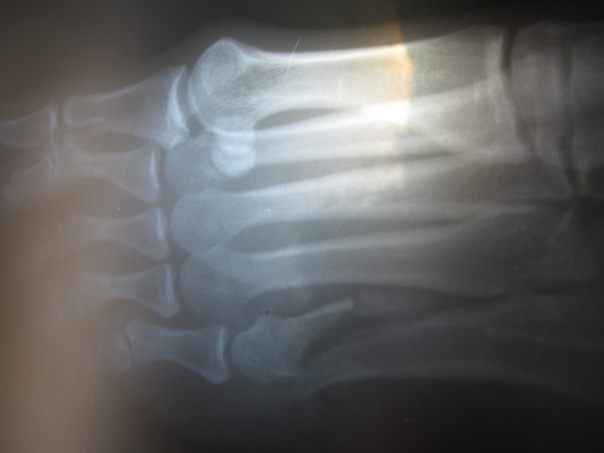

Dancer's Fracture